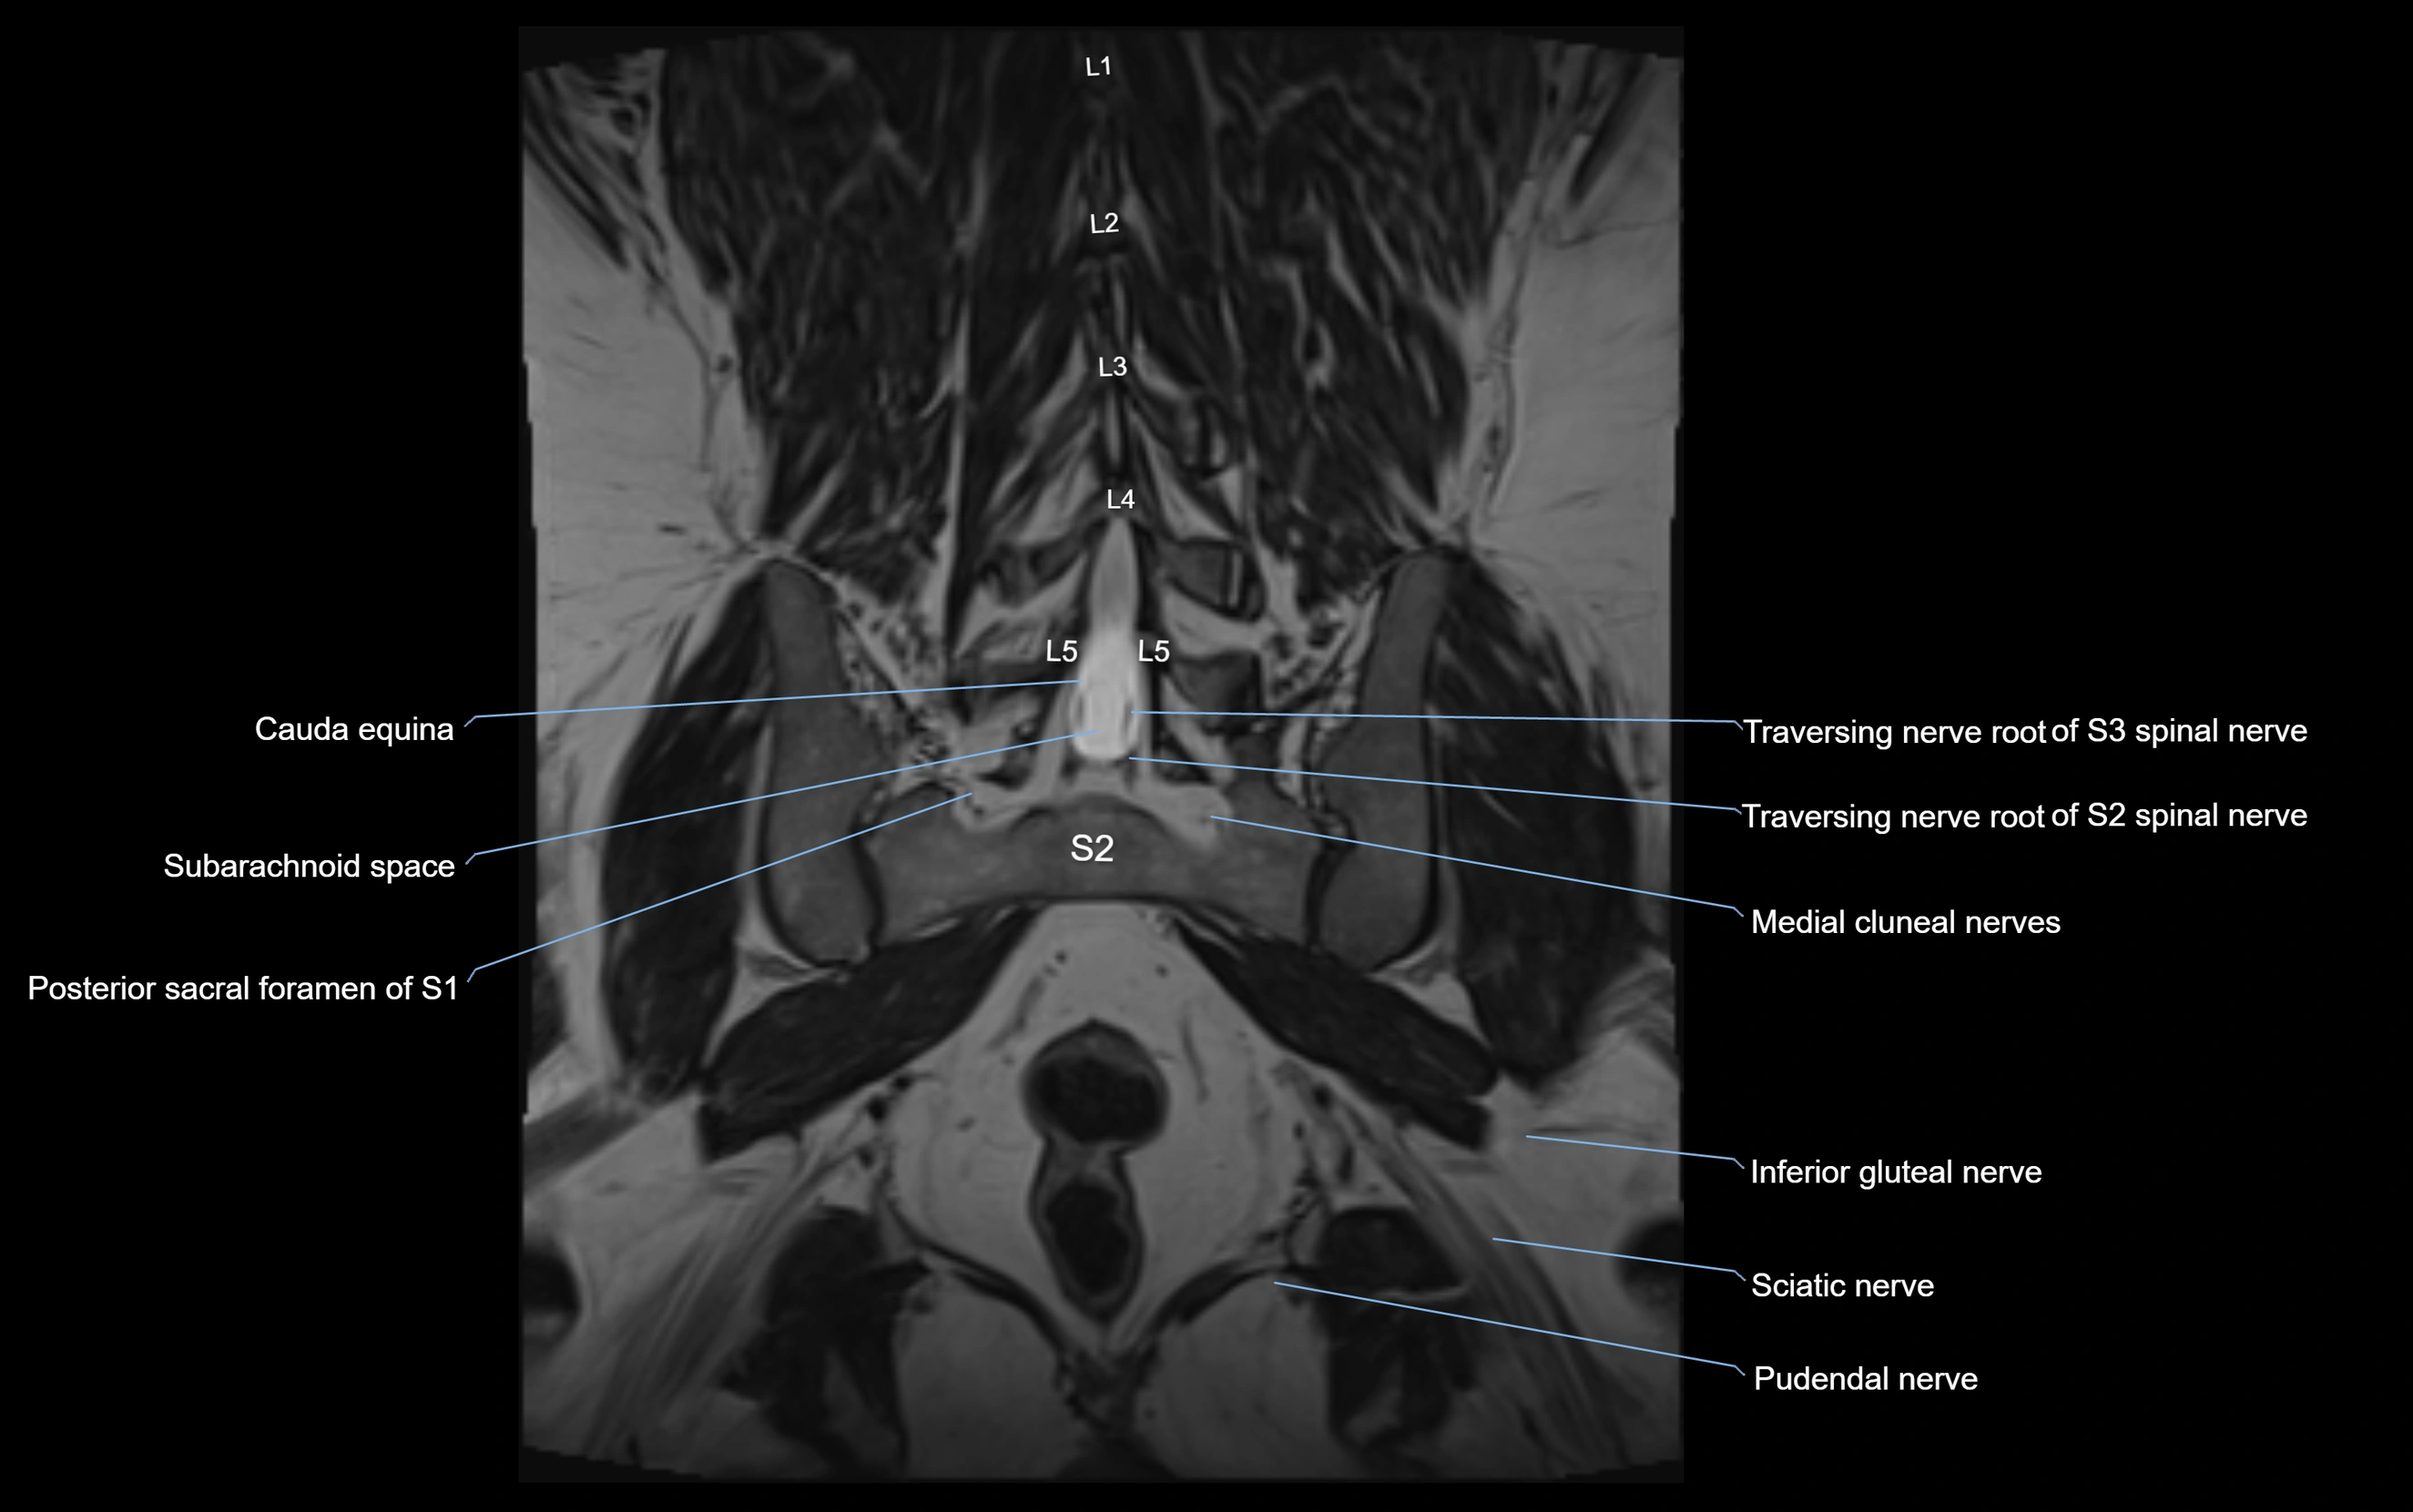

MRI image

image